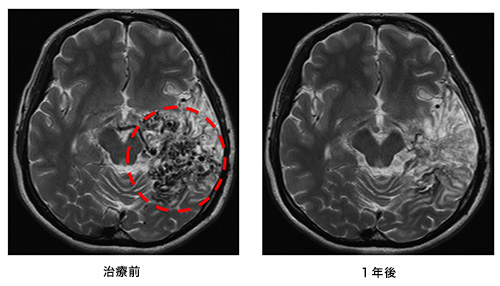

動静脈奇形部分に集中的に放射線を照射する治療法です。小型の病変が治療対象となります。サイバーナイフ治療の前後のMRIと血管撮影の画像を下に提示します。